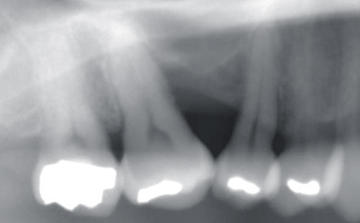

- X線診査(レントゲン)

検査で得たデータをもとに、患者さんのお口の傾向を分析、適切な対処法を決定します。